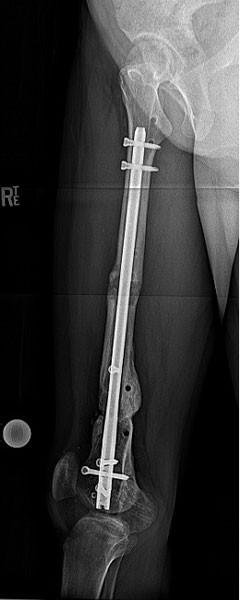

The final xrays show the bone fully healed and straight. Nicole is fully recovered and very pleased. Her leg looks and performs much better than before.